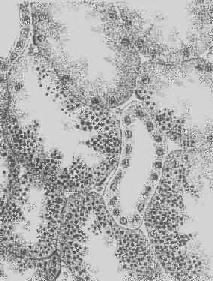

图1-22 肝淀粉样变

淀粉样物质呈均质状,沉着于窦内皮下,肝细胞索受压萎缩